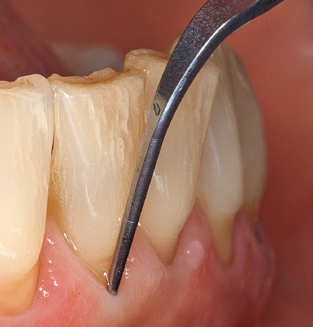

The current working concept for SPT

Fig. 4: Flexible probes with millimetre markings are recommended for the probing of dental implants (e.g. Colorvue Kit PCV11KIT6, Hu­Friedy). – Fig. 5a and b: A straight working tip (1P, W&H Dentalwerk Bürmoos GmbH) is a suitable instrument for use on all natural teeth. – Fig. 6: Curved working tips (3Pr/3Pl, W&H Dentalwerk Bürmoos GmbH) lend themselves to the processing of difficult-to-reach areas of the tooth and root surfaces (e.g. furcations). – Fig. 7: The tapered, hexagonal implant cleaning tip (1I, W&H Dentalwerk Bürmoos GmbH) permits atraumatic and efficient cleaning of the crown and abutment surfaces. – Fig. 8: Titanium and carbon curettes are suitable instruments for the manual cleaning of the implant surfaces.